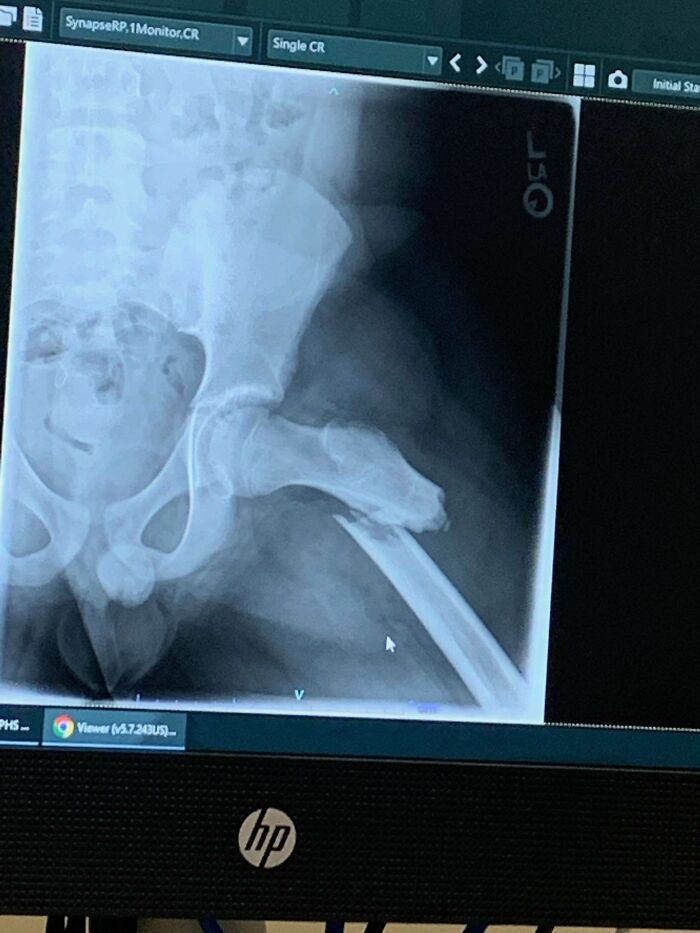

#30 My Hip Died From Avn, Then I Woke Up In The Hospital Recovery Room Not Knowing The Replacement Was Dislocated

Some general info on my situation. Had developed on and off pain in my left leg/hip for years till it got so bad I couldn’t put my full weight on it, which is when I got in for the first image showing an MRI slice of the dead hip. Eventually I was able to get the hip arthroplasty done. I awoke in recovery with my leg flat on the bed. I complained to the initial Nurse’s & PT people that it felt weird & shorter than it should be. The Drs and surgeon said normally patients felt it was longer, but it felt shorter to me and those initial people after the surgery told me that what I felt was “normal”… I figured I just had a hip replacement & it’d be painful… ~1.5 months later they did a Xray & well, that’s why I couldn’t walk like I’d read I should have been able too. Anteriorly dislocated the whole time. I kept bringing it up about it feeling weird with the med related people I was seeing… I suppose I was a bit stoic & didn’t give the right number of the pain that I felt. Just thought they knew better than me. I feel like I have a permanent muscle knot at this point.

Image source: SomeDumbPenguin